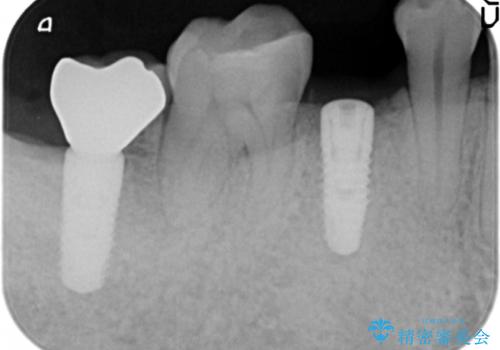

- 奥歯(右下5)のインプラントをご希望し来院された患者様です。

なるべく低予算でとのご希望により、アルファタイトインプラント(保証期間:3年)による治療を行いました。

インプラントの種類:アルファタイト

クラウンの種類:オールセラミッククラウン スタンダード